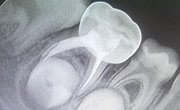

Our state-of-the-art manufacturing process for preformed dental crowns ensures highly accurate, custom-fit restorations, enhancing both clinical outcomes and patient satisfaction.

With faster production times, enhanced durability, and a more comfortable fit, Rainbow Crown elevates the standard of care for both practitioners and patients, setting a new benchmark for modern dental restorations.